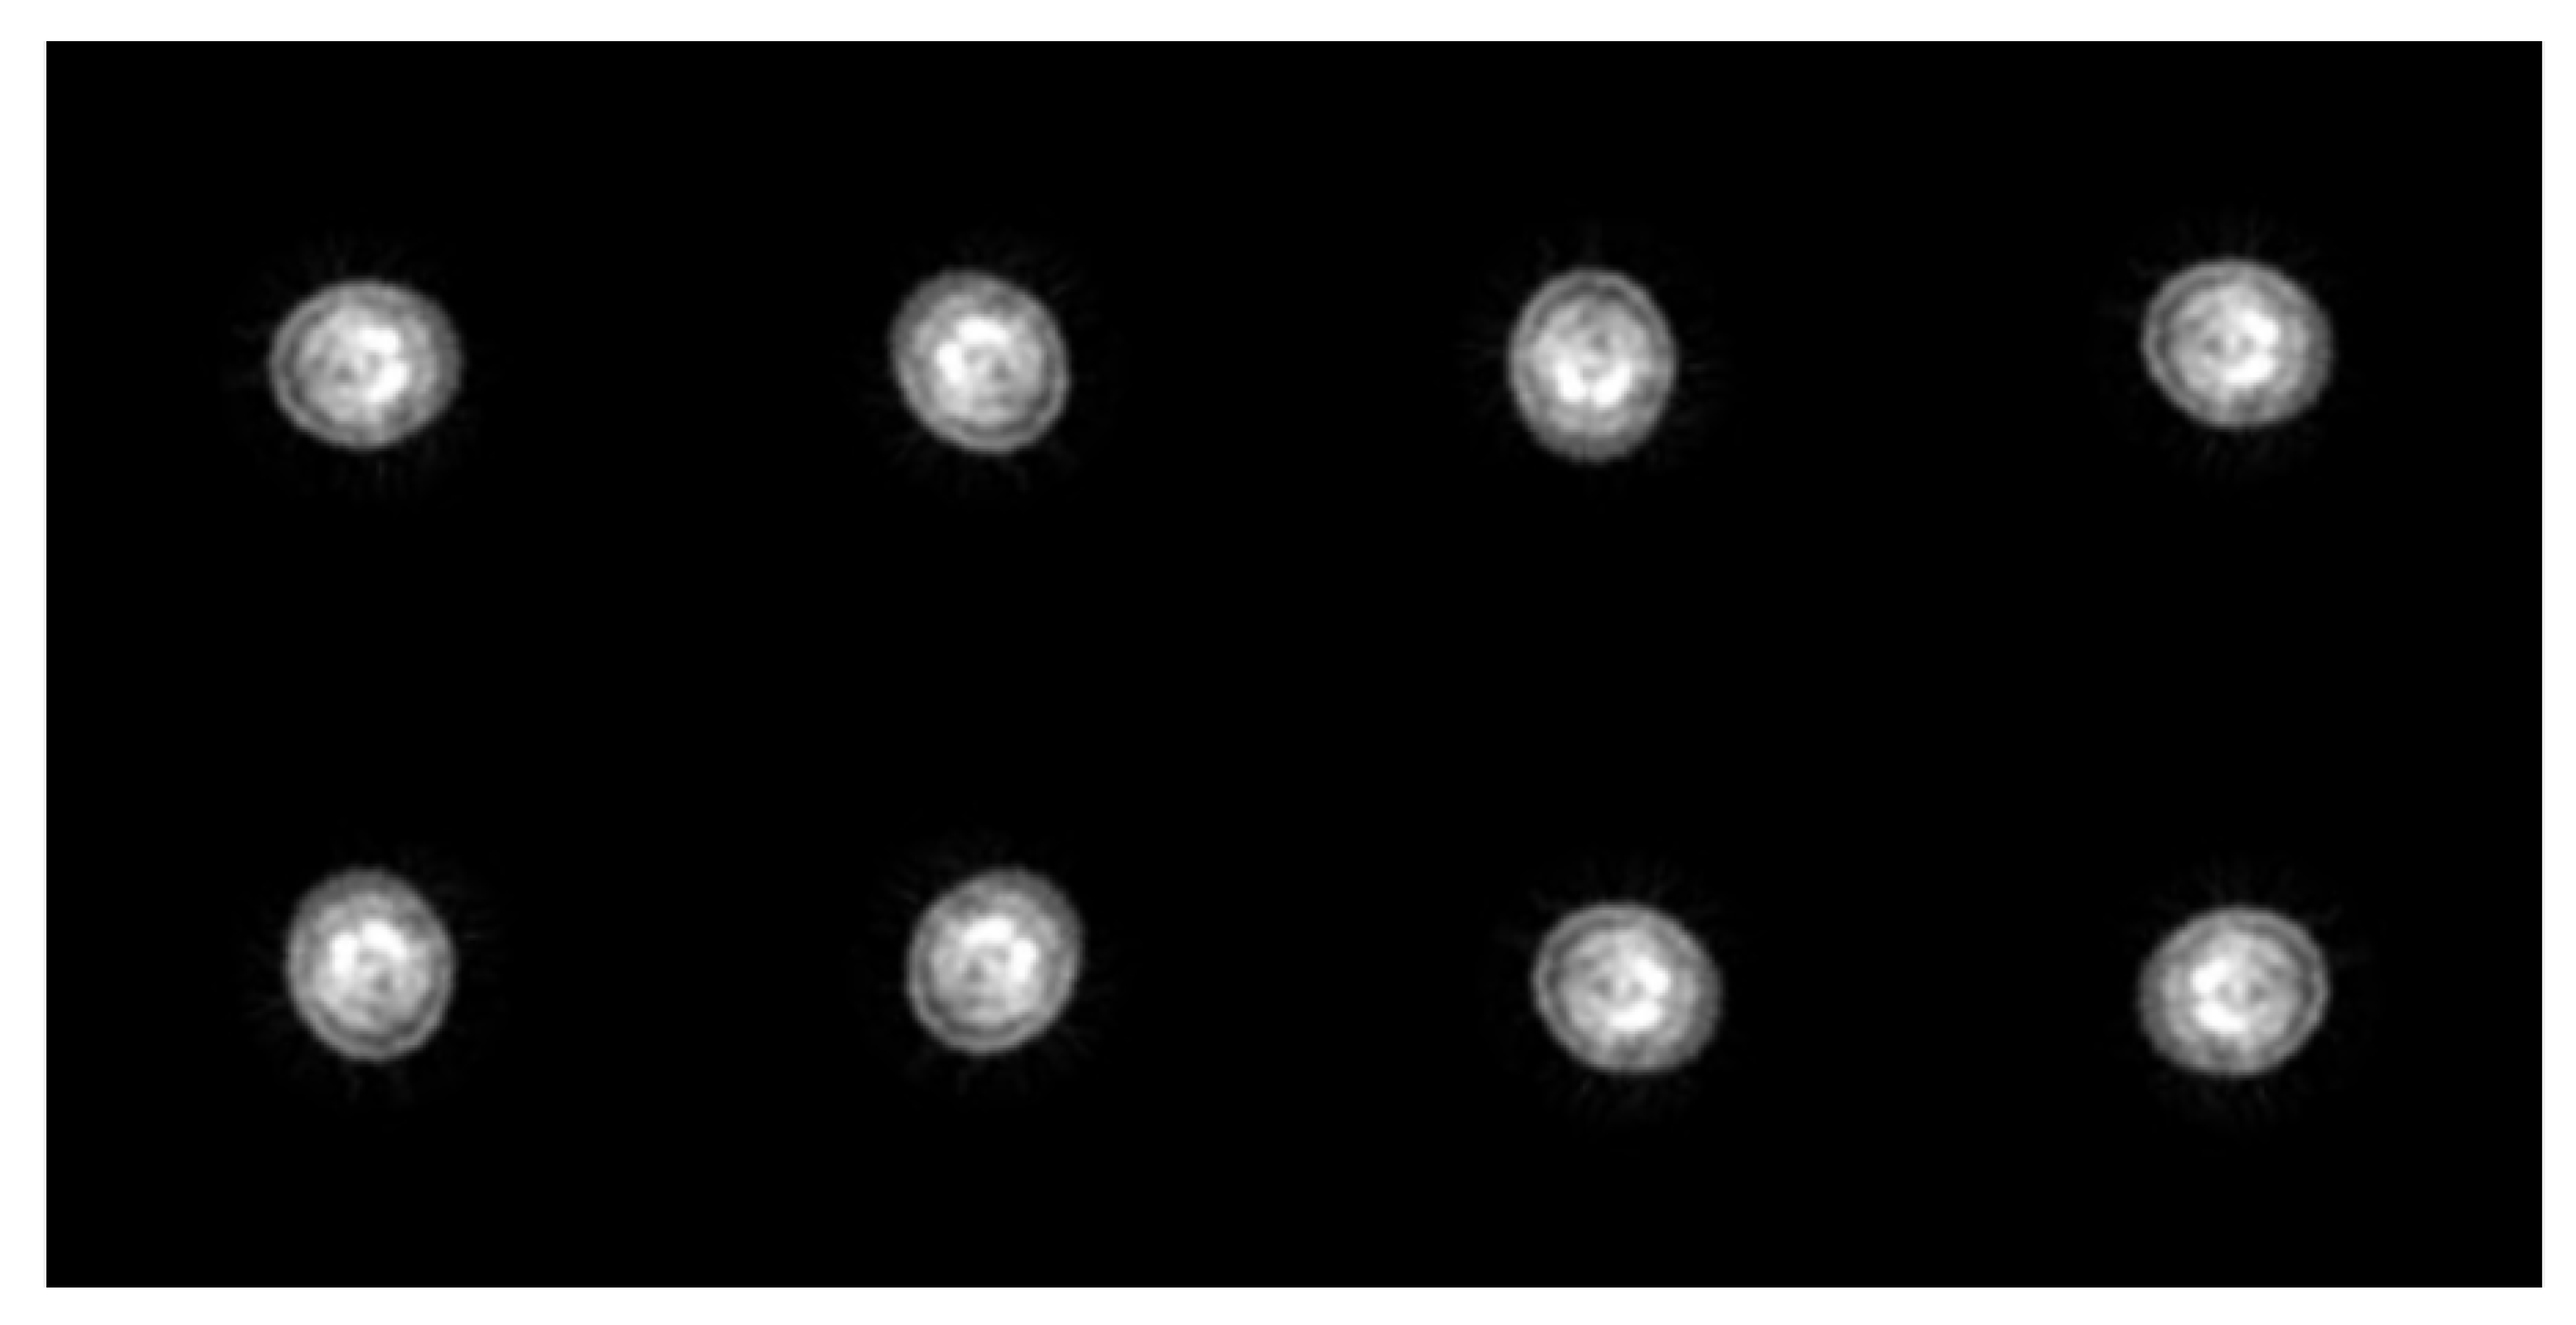

2.2. The Imaging Conditions of 99mTc TRODAT-1 SPECT

2.3. The Deep Learning Method Concept